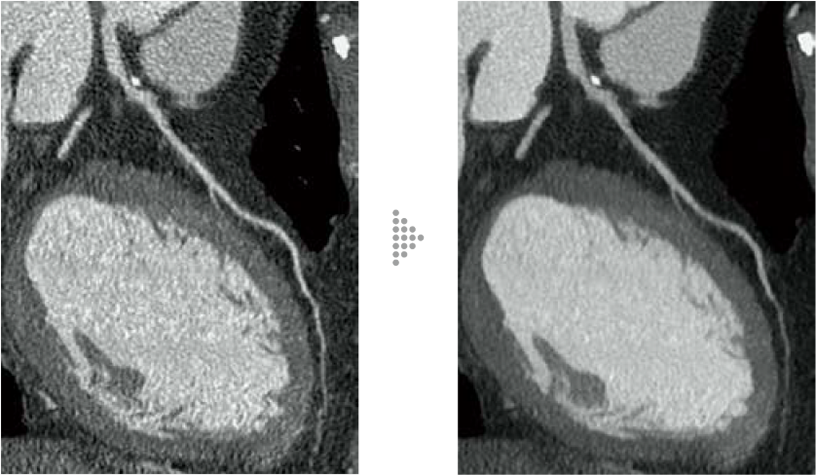

Applying Intelli IPV*1*2, which utilizes Fujifilm's AI technology, to cardiac CT realizes high image quality with lower noise and maintained texture even in low tube voltage imaging and at low radiation doses. Cardiac CT imaging has become even more accessible.

FBP(Left)

Intelli IPV(Right)